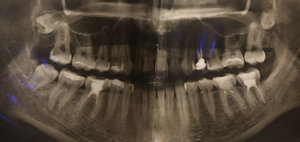

Сломала пол переднего резца. Поставили световую пломбу, была довольна. Со временем зуб потемнел, и граница пломбы стала видна, да и сама пломба сточилась немного. Можно ли ее заменить под более подходящий цвет зуба?

Добрый день. Да, конечно можно, но я вам рекомендую изготовить терапевтический винир, то есть необходимо перекрыть всю фронтальную часть зуба, чтобы избежать трещин пломбы на границах с зубом либо установить коронку.

Оба метода актуальны и правильны, все зависит от ситуации и объема оставшихся тканей зуба!